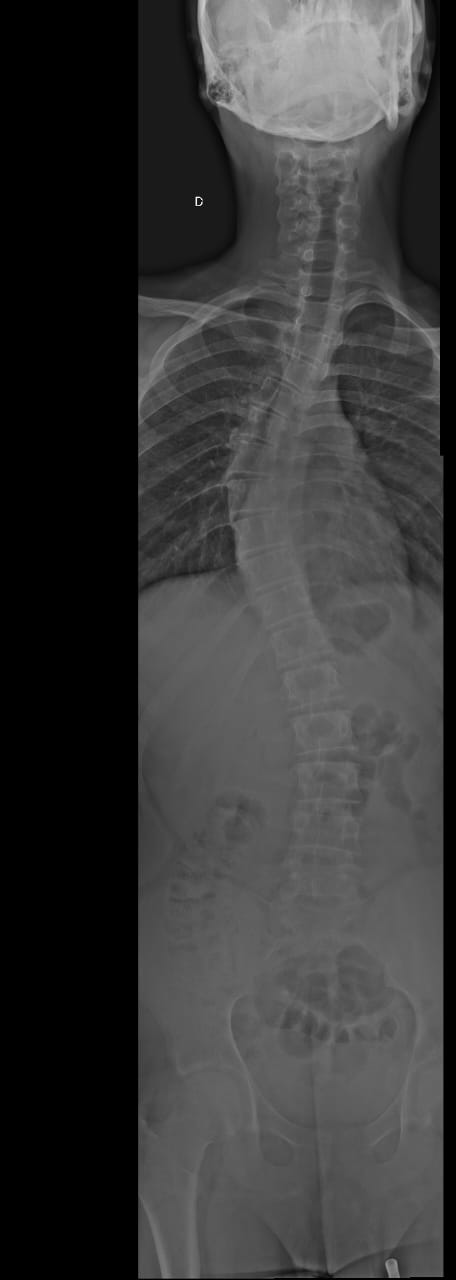

Matheus tem escoliose em grau avançado (curvatura em S de 42 graus), o que tem afetado profundamente sua qualidade de vida. Estamos em uma verdadeira batalha por exames e atendimentos médicos, muitos deles em outras cidades, o que gera gastos com transporte e alimentação que hoje não consigo cobrir.

Além da escoliose, Matheus também precisa de acompanhamento com neuropsicólogo e sofre de asma respiratória, o que exige cuidados constantes. No momento, estamos aguardando uma tomografia da coluna, exame essencial para avaliar a necessidade de cirurgia, conforme já indicado pelo médico. Também preciso providenciar óculos novos para ele, mas infelizmente estou sem condições financeiras.